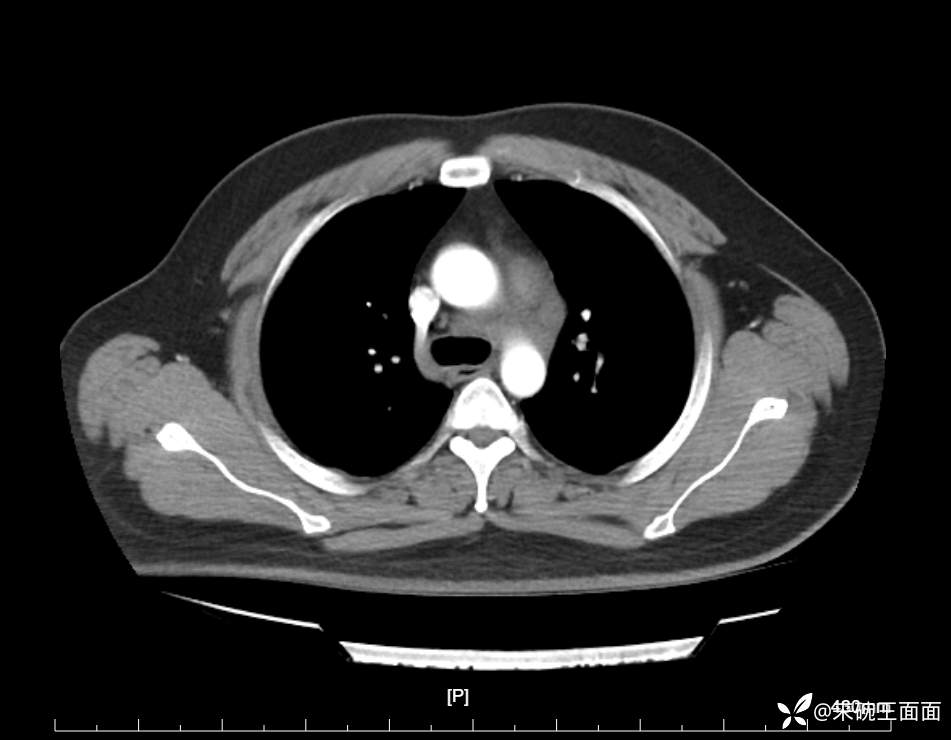

性别:男

年龄:27岁

主诉:胸闷胸痛数月余,休息后可自行缓解,无咯血症状。

个人史:数年吸烟史,具体不详。